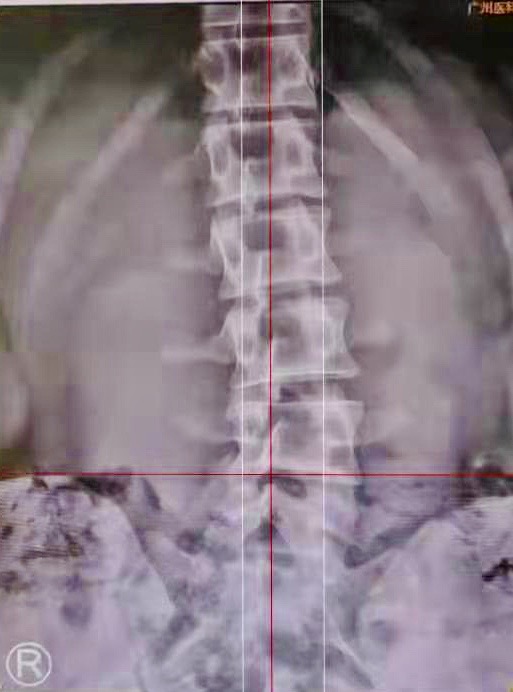

广医三院中医科主任中医师胥海斌为他做了详细检查,发现他腰椎4、5椎间盘轻度膨出,腰4椎体向后移位,椎体还出现一定程度的扭转,同时伴有脊柱侧弯。

图左:正常的腰椎间盘有向内凹的曲线;图右:阿浩的腰椎间盘向外轻度膨出。

阿浩还伴有脊柱侧弯。